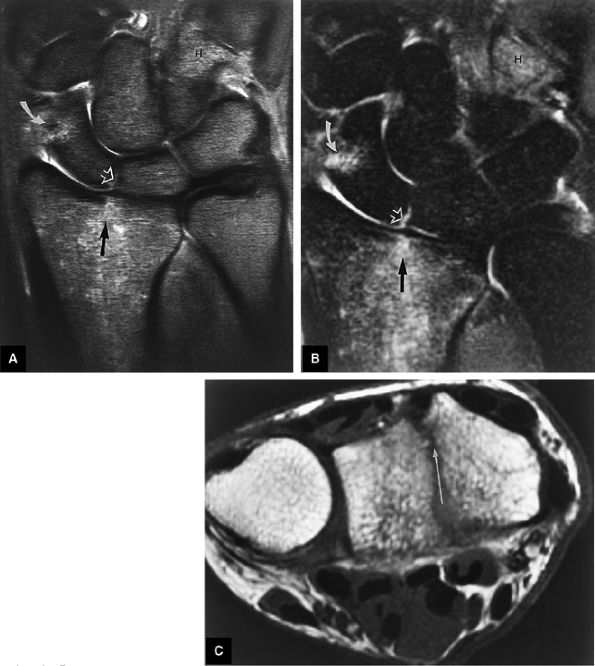

FIGURE 10.2 ● Optimized signal-to-noise in routine wrist imaging using a four-channel phased-array wrist coil on a 3T imager. (A) Coronal PD FSE image. (B) Coronal FS PD FSE image. (C) Axial PD FSE image.